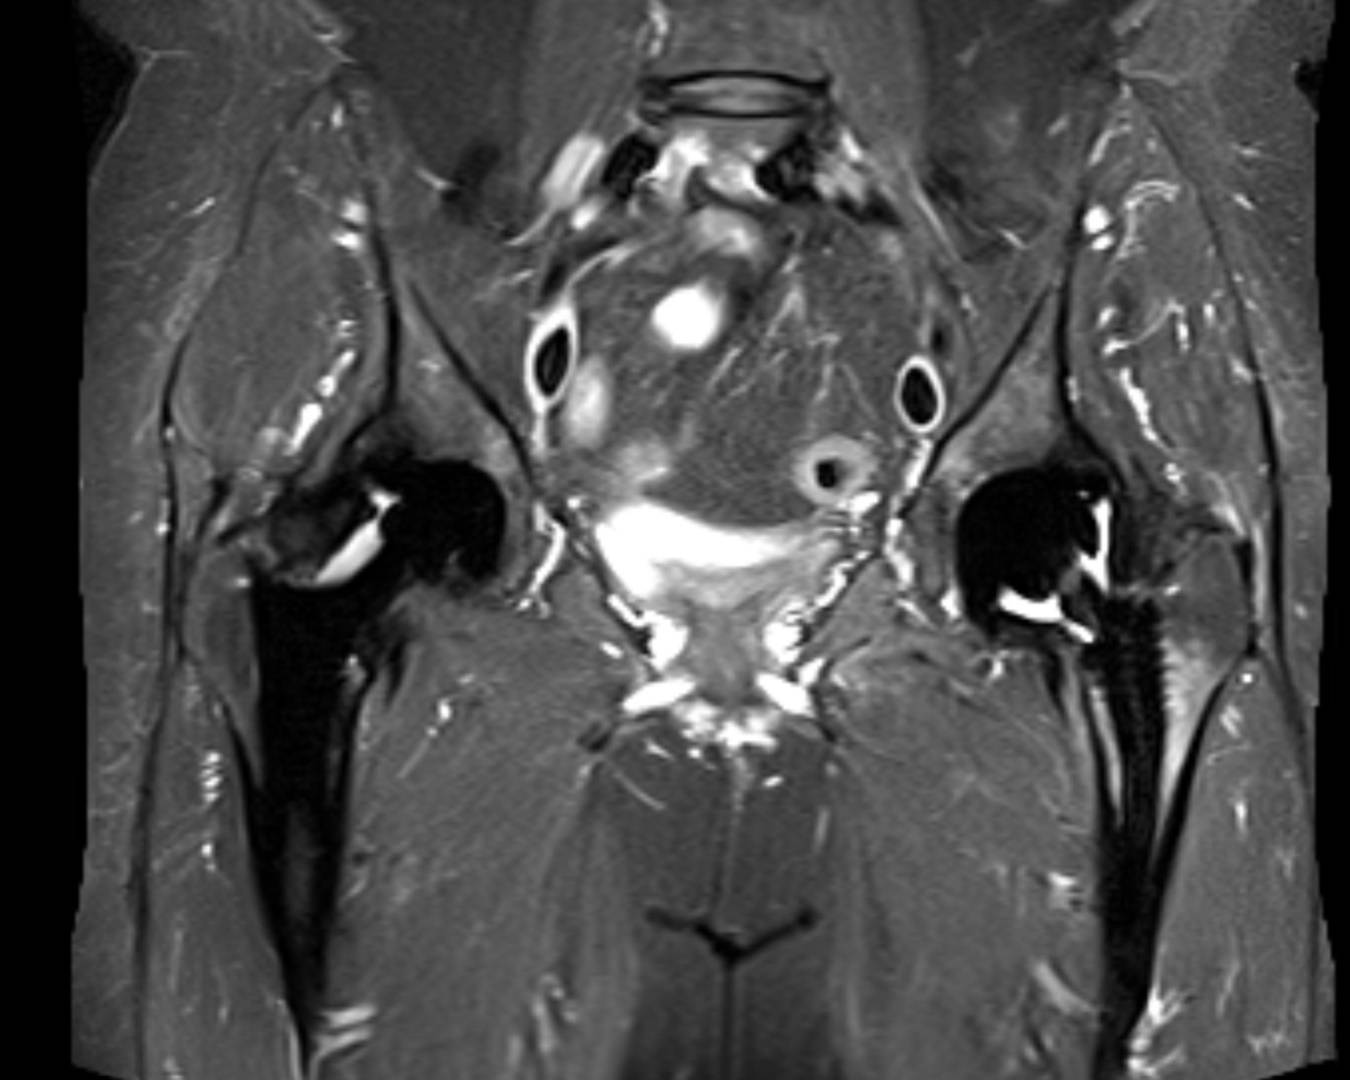

Kann man eine Entzündung im MRT sehen? Ob Knochen, Muskeln, Sehnen, Bänder oder Knorpel - mit einer MRT-Untersuchung können Schädigungen, Veränderungen, Entzündungen und grobe Verkalkungen am gesamten Bewegungsapparat exakt beurteilt werden. Besonders hervorzuheben ist jedoch die Rolle des MRT im Kontext entzündlich-rheumatischer Erkrankungen wie der Rheumatoiden Arthritis, dem Morbus Bechterew, der Psoriasis Arthritis oder der reaktiven Arthritis

Besonders hervorzuheben ist jedoch die Rolle des MRT im Kontext entzündlich-rheumatischer Erkrankungen wie der Rheumatoiden Arthritis, dem Morbus Bechterew, der Psoriasis Arthritis oder der reaktiven Arthritis Bei diesen Autoimmunerkrankungen sind häufig Gelenke und Weichteile wie etwa Sehnenansätze entzündet. Die weißen Flecken, die man auf MRT-Bildern sieht, stellen Flüssigkeit dar